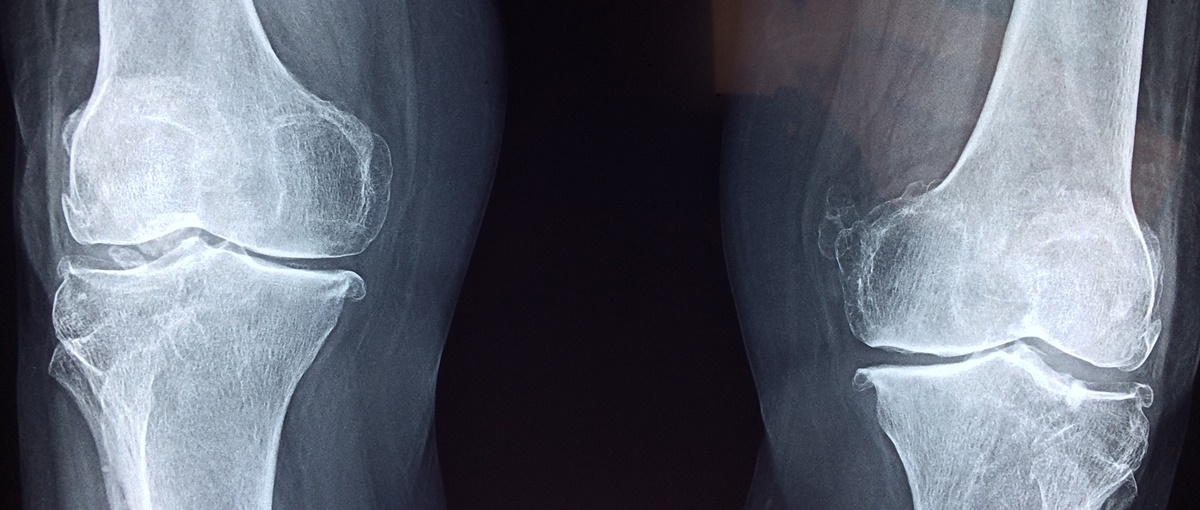

Osteoporoza u prevodu znači “porozna kost ”. Gledano pod mikroskopom, zdrava kost je oblika pčelinjeg saća. Kada se pojavi osteoporoza, rupe i prostori u koštanom “saću” su mnogo veći nego kod zdravih kostiju. Osteoporotične kosti su izgubile gustinu i/ili masu i imaju abnormalnu strukturu tkiva. Pošto kostima opada gustina, one su slabe i lakše dolazi do njihovog preloma.